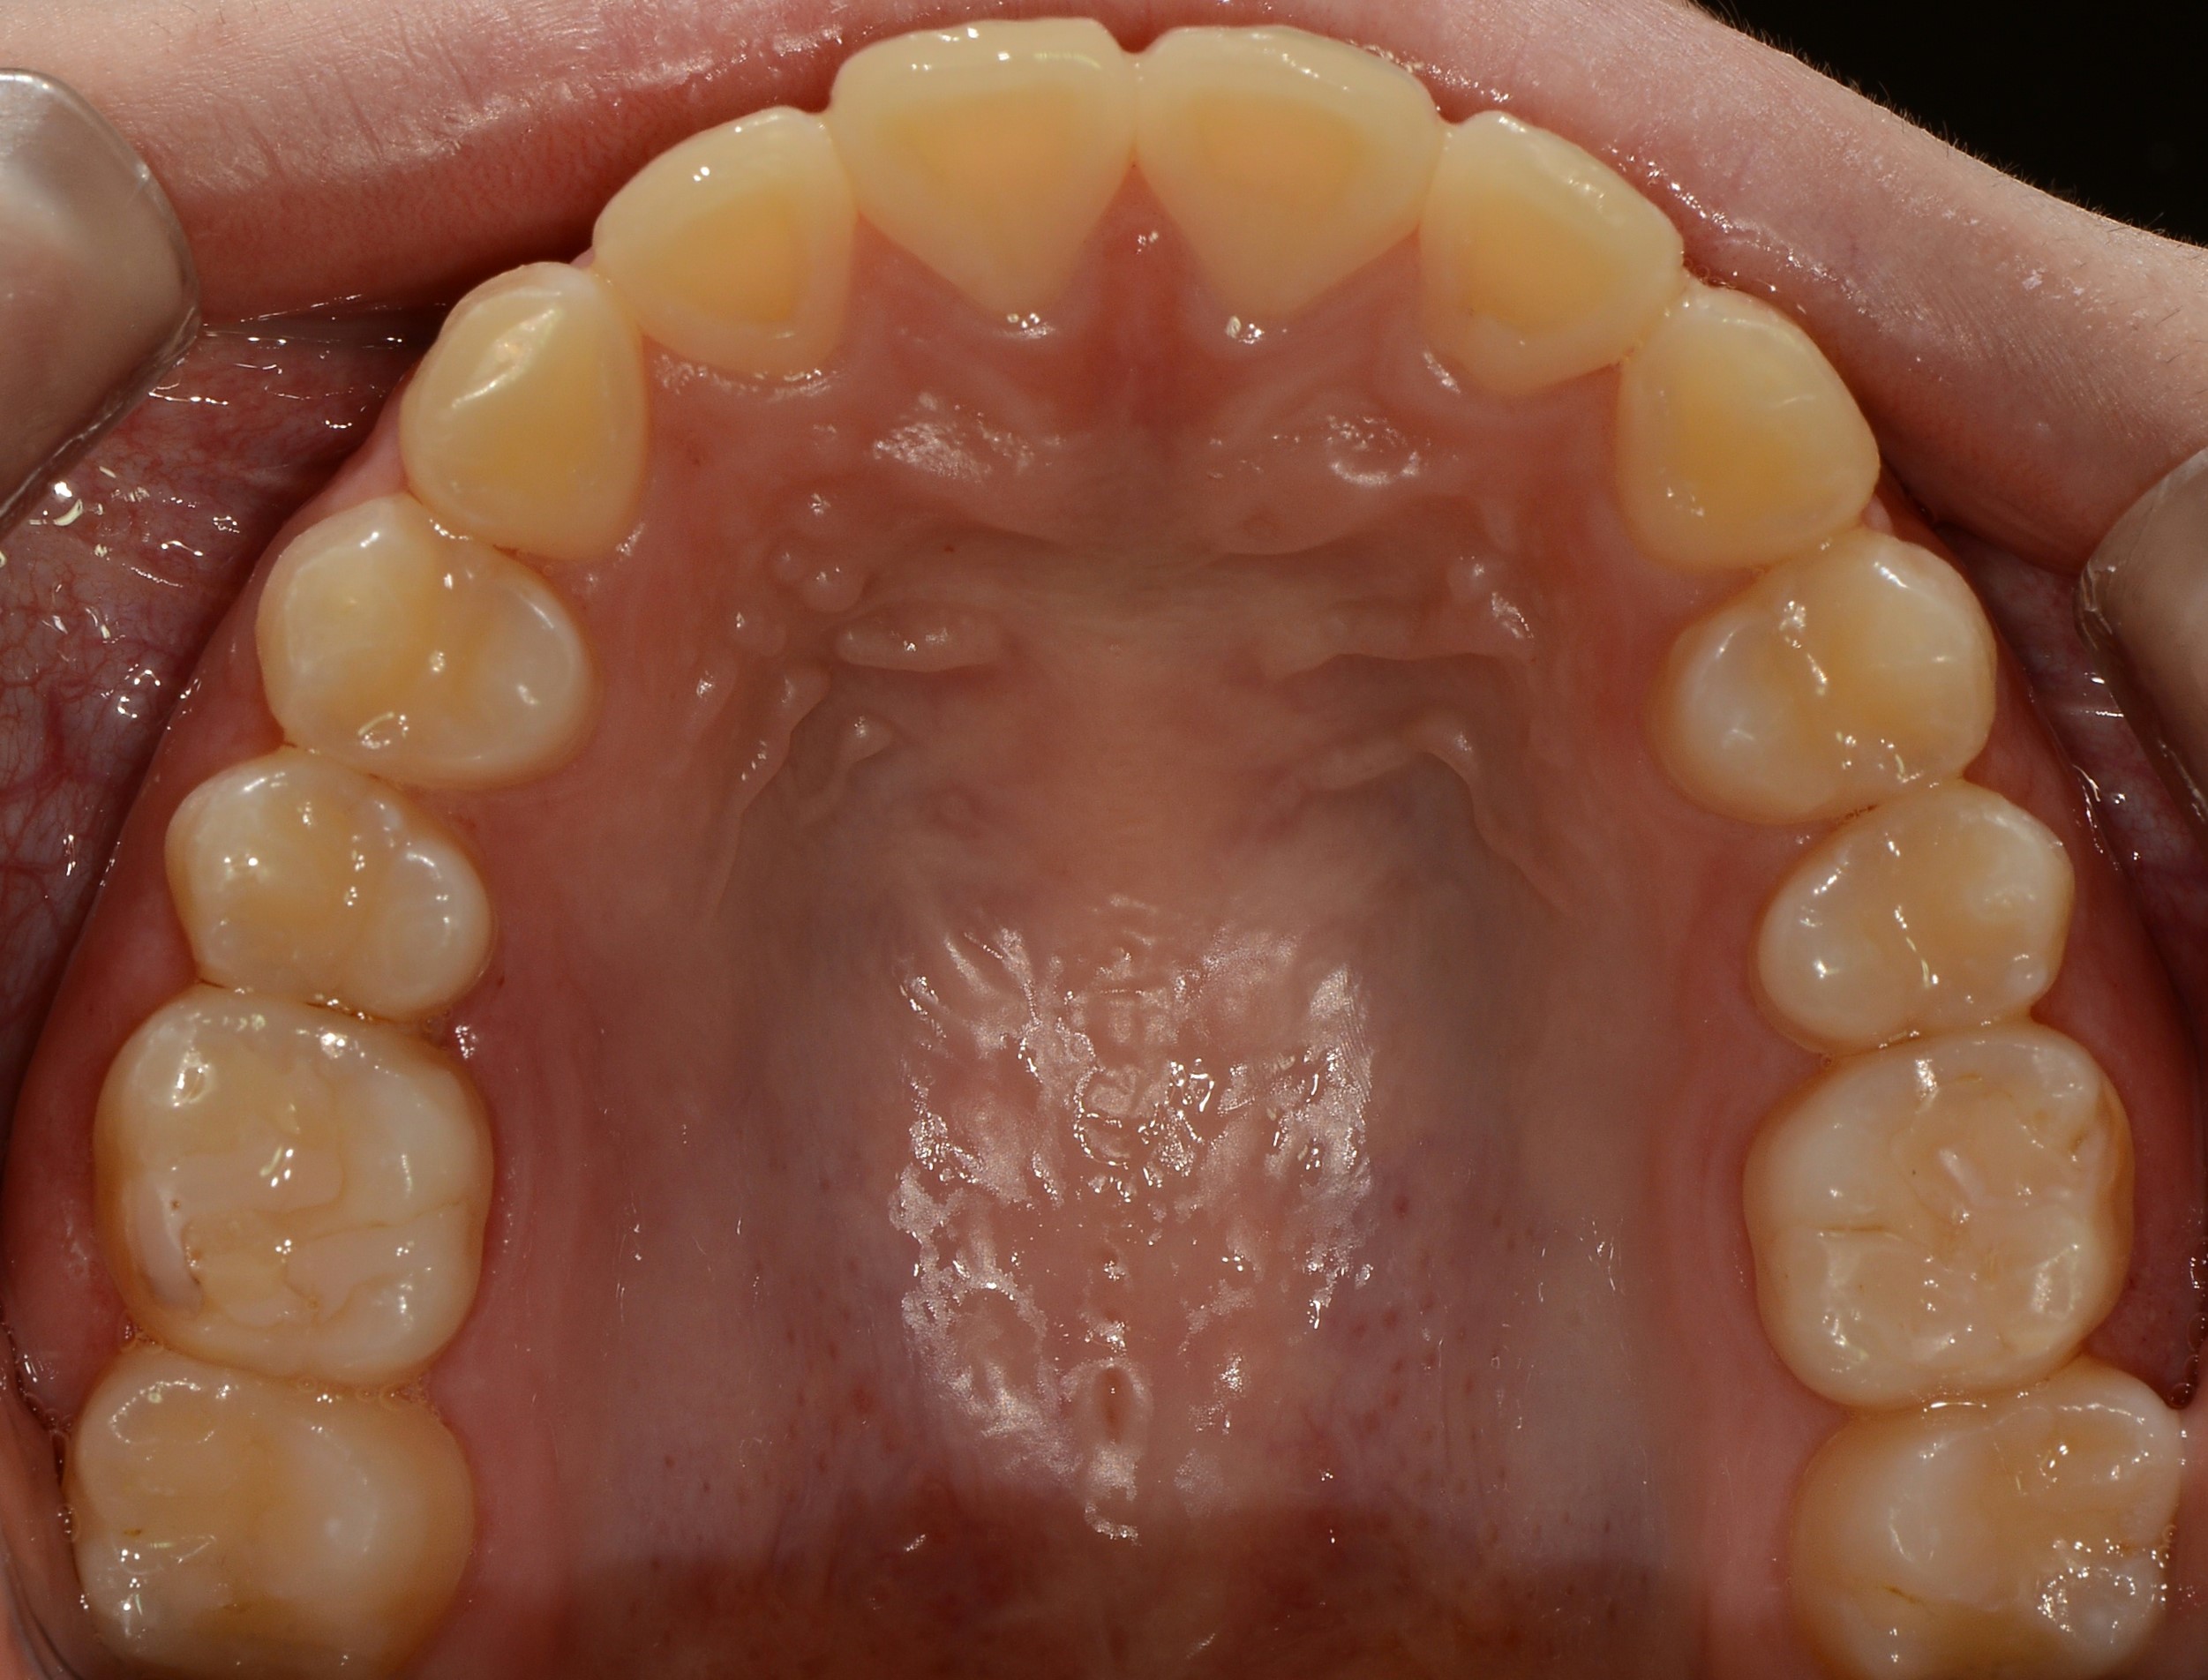

치료 후 사진입니다.